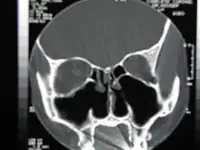

CT scan of the nose after total bilateral turbinectomy/turbinoplasty

A turbinectomy or turbinoplasty (preserving the mucosal layer) is a surgical procedure, that removes tissue, and sometimes bone, of the turbinates in the nasal passage, particularly the inferior nasal concha. The procedure is usually performed to relieve nasal obstructions.[1] In most cases, turbinate hypertrophy is accompanied by some septum deviation, so the surgery is done along with septoplasty.[2]